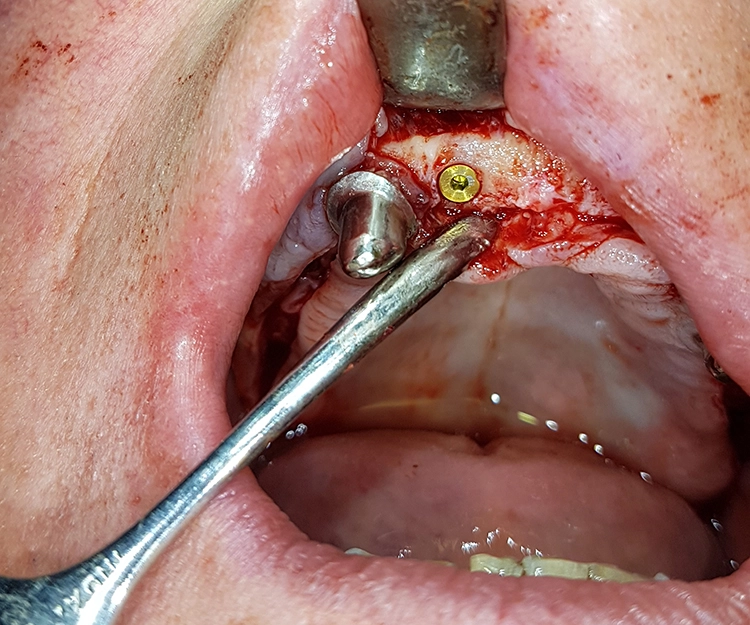

Extraktion und Alveolenmanagement

Die Freilegung der Implantate erfolgte mit minimalinvasiver Stichinzision. Die Verschlussschrauben wurden entfernt und Gingivaformer eingesetzt, um das Weichgewebe auszuformen. Die ursprüngliche Teleskopprothese wurde im Bereich der Gingivaformer ausgeschliffen und mit einer Gaumenplatte erweitert.

So konnte sie als Interimsversorgung, verankert auf den Zähnen 23 und 24, über den Gingivaformern als Interimsersatz genutzt werden und sich das Weichgewebe unbelastet um die Implantate herum ausformen. Einige Wochen später – wiederum verzögert durch einen Campingaufenthalt – konnte auf dem mittlerweile befestigten und stabilen Weichgewebe für die Herstellung der definitiven Restaurationen abgeformt werden. Hier ist von Vorteil, dass die Conelog Abformpfosten nicht in den Konus des Implantats eingreifen, sondern auf der Implantatschulter aufliegen, wodurch ein Höhenversatz bei der Abformung vermieden wird.

Zeitgleich mit der Freilegung wurde Zahn 13 extrahiert. Nach sorgfältiger Exkochleation wurde die unversehrte Alveole im Sinne einer Socket Preservation mit bovinem Knochenersatzmaterial (MinerOss X) verfüllt und mit einer porcinen Kollagenmembran (MemLok Pliable) abgedeckt. Damit lässt sich ein postoperativer Gewebeabbau und eine Einschränkung der Weichgewebeästhetik unter einem Brückenglied weitgehend vermeiden: Die Socket Preservation mit bovinem Knochenmineral und porciner Kollagenmembran schränkt die horizontale und vertikale Knochenresorption im Vergleich zur alleinigen Extraktion erheblich ein (Abb. 19 und 20) [1,6,9].